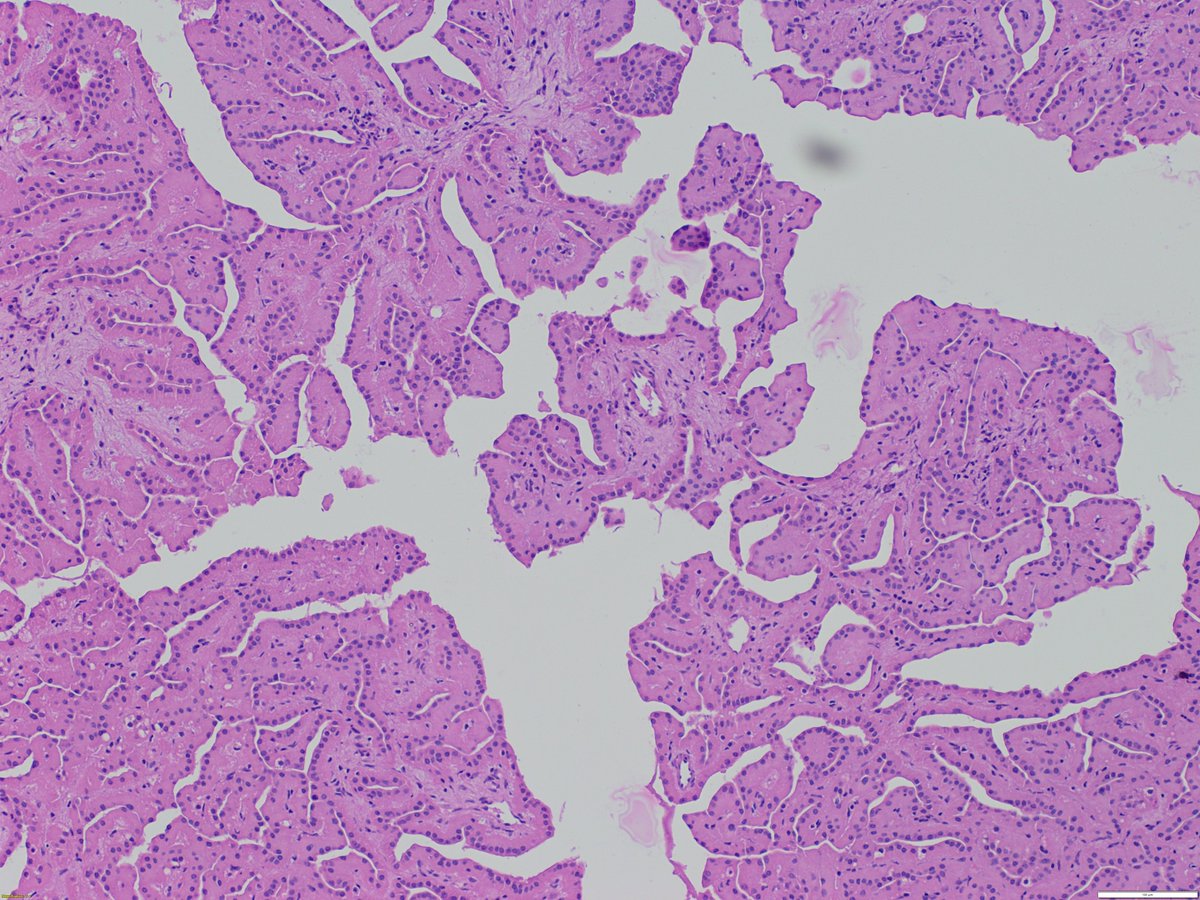

May is #bladdercancerawarenessmonth - important to recognize lesions which mimic #bladdercancer Nephrogenic metaplasia/adenoma: - various architectures (papillary, tubular/glandular, vascular-like...) - cuboidal to hobnail nuclear features - prominence of basement membrane